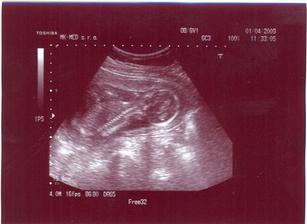

Prvá poradňa bude 2.3.2009. V Poradni všetko OK. UTZ u Dr. Čunderlíka 4.3.2009. Všetko v norme (chvalabohu). Zmenili mi TP zo 4.9.2009 na 13.9.2009. Ďalšia poradňa bude 1.4.2009. V poradni všetko OK. Už len ako dopadnú výsledky z genetiky (7.4.2009). Držte prosím všetci palce. Huráááááááááá AFP testy po opakovaní vyšli super. Konečne budeme mať pokoj. Fuj to bolo dosť zlé ale je to za nami. Už sa len tešiť na bábulko 🙂. Ďalšia poradňa bude 4.5.2009. Snáď uvidíme výbavu 🙂. 25.4.2009 som cítila prvý pohyb (zatiaľ len jeden) 🙂. 29.4.2009 bolo pohybov viacej 🙂)))))). V poradni všetko OK. Asi to bude dievčatko 🙂)))))))))))))))))))))))))). Snáď budem múdrejšia 6.5. 2009 na morfológii. Takže dievčatko to teda nebude 🙂))). Je tam pipík ako hrom. Tešíme sa na Teba synček!!! 20.5.2009 idem na glukózové testy, či nemám tehotenskú cukrovku. Dúfam, že to bude negatívne. Ďalšia poradňa bude 1.6.2009.